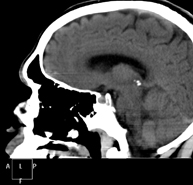

- Neurorradiología- TC Cráneo Prueba radiológica que consiste en obtener imágenes del cráneo de alta definición anatómica (tronco cerebral, cerebelo, cerebro, calota craneal, etc.), mediante el empleo de un equipo de TC (Tomografía Computarizada).Indicaciones: traumatismos, cefalea, trastornos de la memoria, pérdida de fuerza súbita en una extremidad o mitad del cuerpo. Prueba radiológica que consiste en obtener imágenes del cráneo de alta definición anatómica (tronco cerebral, cerebelo, cerebro, calota craneal, etc.), mediante el empleo de un equipo de TC (Tomografía Computarizada).Indicaciones: traumatismos, cefalea, trastornos de la memoria, pérdida de fuerza súbita en una extremidad o mitad del cuerpo.